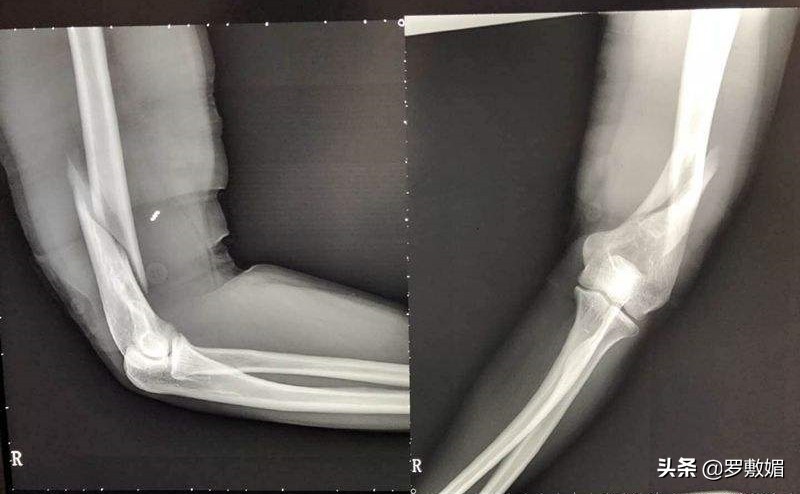

班主任二话不说,立即开车把邵某轩送回家,邵某轩的父母见病情严重,和班主任一起送到了东营市人民医院急救室。经CT扫描检查,邵某轩被确诊为左臂肱骨粉碎性骨折。

肱骨骨折图

案件审理过程中,法院委托利津县中心医院司法鉴定所出具了司法鉴定意见:邵某轩左肱骨骨折神经损伤致左肘活动障碍,评定为十级伤残,是最轻微的伤残等级,表现在日常活动能力部分受限、工作和学习能力有所下降;社会交往能力部分受限。